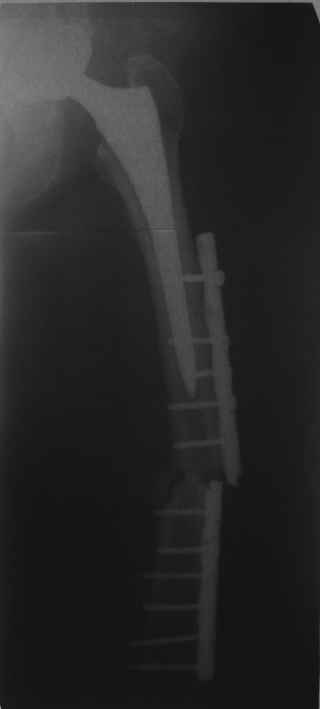

Обещанные ранее снимки Заранее спасибо.

Хотел бы обратить Ваше внимание, что реакция кортикала наблюдается только вокруг проксимального винта, дистальный винт не испытывает подобной нагрузки. Отсюда еще одна умозрительная авантюра - выкрутить только проксимальный винт. Изменения кости вокруг дистального винта тоже могут дать ответ на счет интеграции ножки, также как и появляется возможность сломать его. Страховаться (затратнее, но надежнее) или нет(легче, но не безопасно) динамическим винтом - на Ваш выбор.

О качестве сращения перелома тоже сказать трудно. Выраженной мозоли нет. В боковой проекции отломки накладываются друг на друга. В прямой проекции зона перелома в наружной части закрылась не полностью. Возможно причина тому - недогрузка кости.